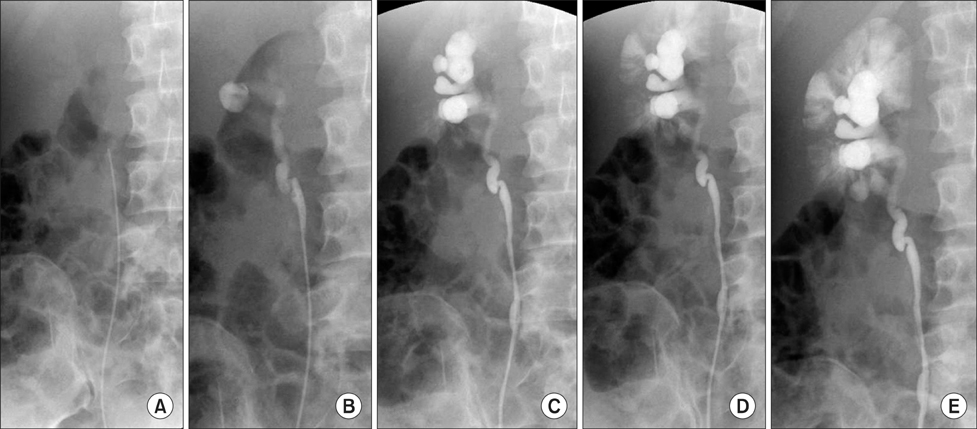

역행성 신우조영술(Retrograde Pyelography)은 방광경(Ureteroscope)을 이용하여 요관을 통해 조영제를 직접 주입한 후, 신우 및 요관을 촬영하는 검사이다. 주로 배설성 요로조영술(IVP)로 확인이 어려운 경우 추가적으로 시행되며, 요관 폐색이나 협착이 의심되는 환자에게 유용하다.

이 검사는 방광경을 통해 요관 카테터를 삽입한 후 조영제를 직접 신우 및 요관으로 주입하여, 요로 폐색이나 협착 부위를 정밀하게 평가하는 방식이다. 조영제는 요관과 신우의 형태를 더욱 선명하게 보여주어 요로계의 이상을 확인하는 데 도움을 준다.

4. 검사 과정

- 방광경 삽입

- 환자는 검진대에 눕고 국소마취를 시행한 후 방광경을 삽입한다.

- 요관 카테터 삽입 및 조영제 주입

- 방광경을 통해 요관에 가느다란 카테터를 삽입한 후 조영제를 직접 주입한다.

- X-ray 촬영

- 조영제가 신우 및 요관으로 흐르는 과정을 X-ray로 촬영한다.

- 필요 시 추가 영상 촬영을 진행할 수 있다.

6. 검사 결과 해석

정상 소견

- 조영제가 신우 및 요관을 따라 원활하게 흐르며, 폐색이나 협착이 없는 경우.

이상 소견

- 요로결석: 요관 내 조영제 흐름이 차단되는 부위가 관찰됨.

- 종양 및 협착: 신장이나 요관 내 이상 구조가 확인됨.

- 요로 감염: 신우신염 등의 감염성 질환에서 신장의 조영제 분포가 비대칭적으로 나타날 수 있음.

- 기형: 선천성 신장 기형, 이중 요관, 방광 구조 이상 등이 확인될 수 있음.